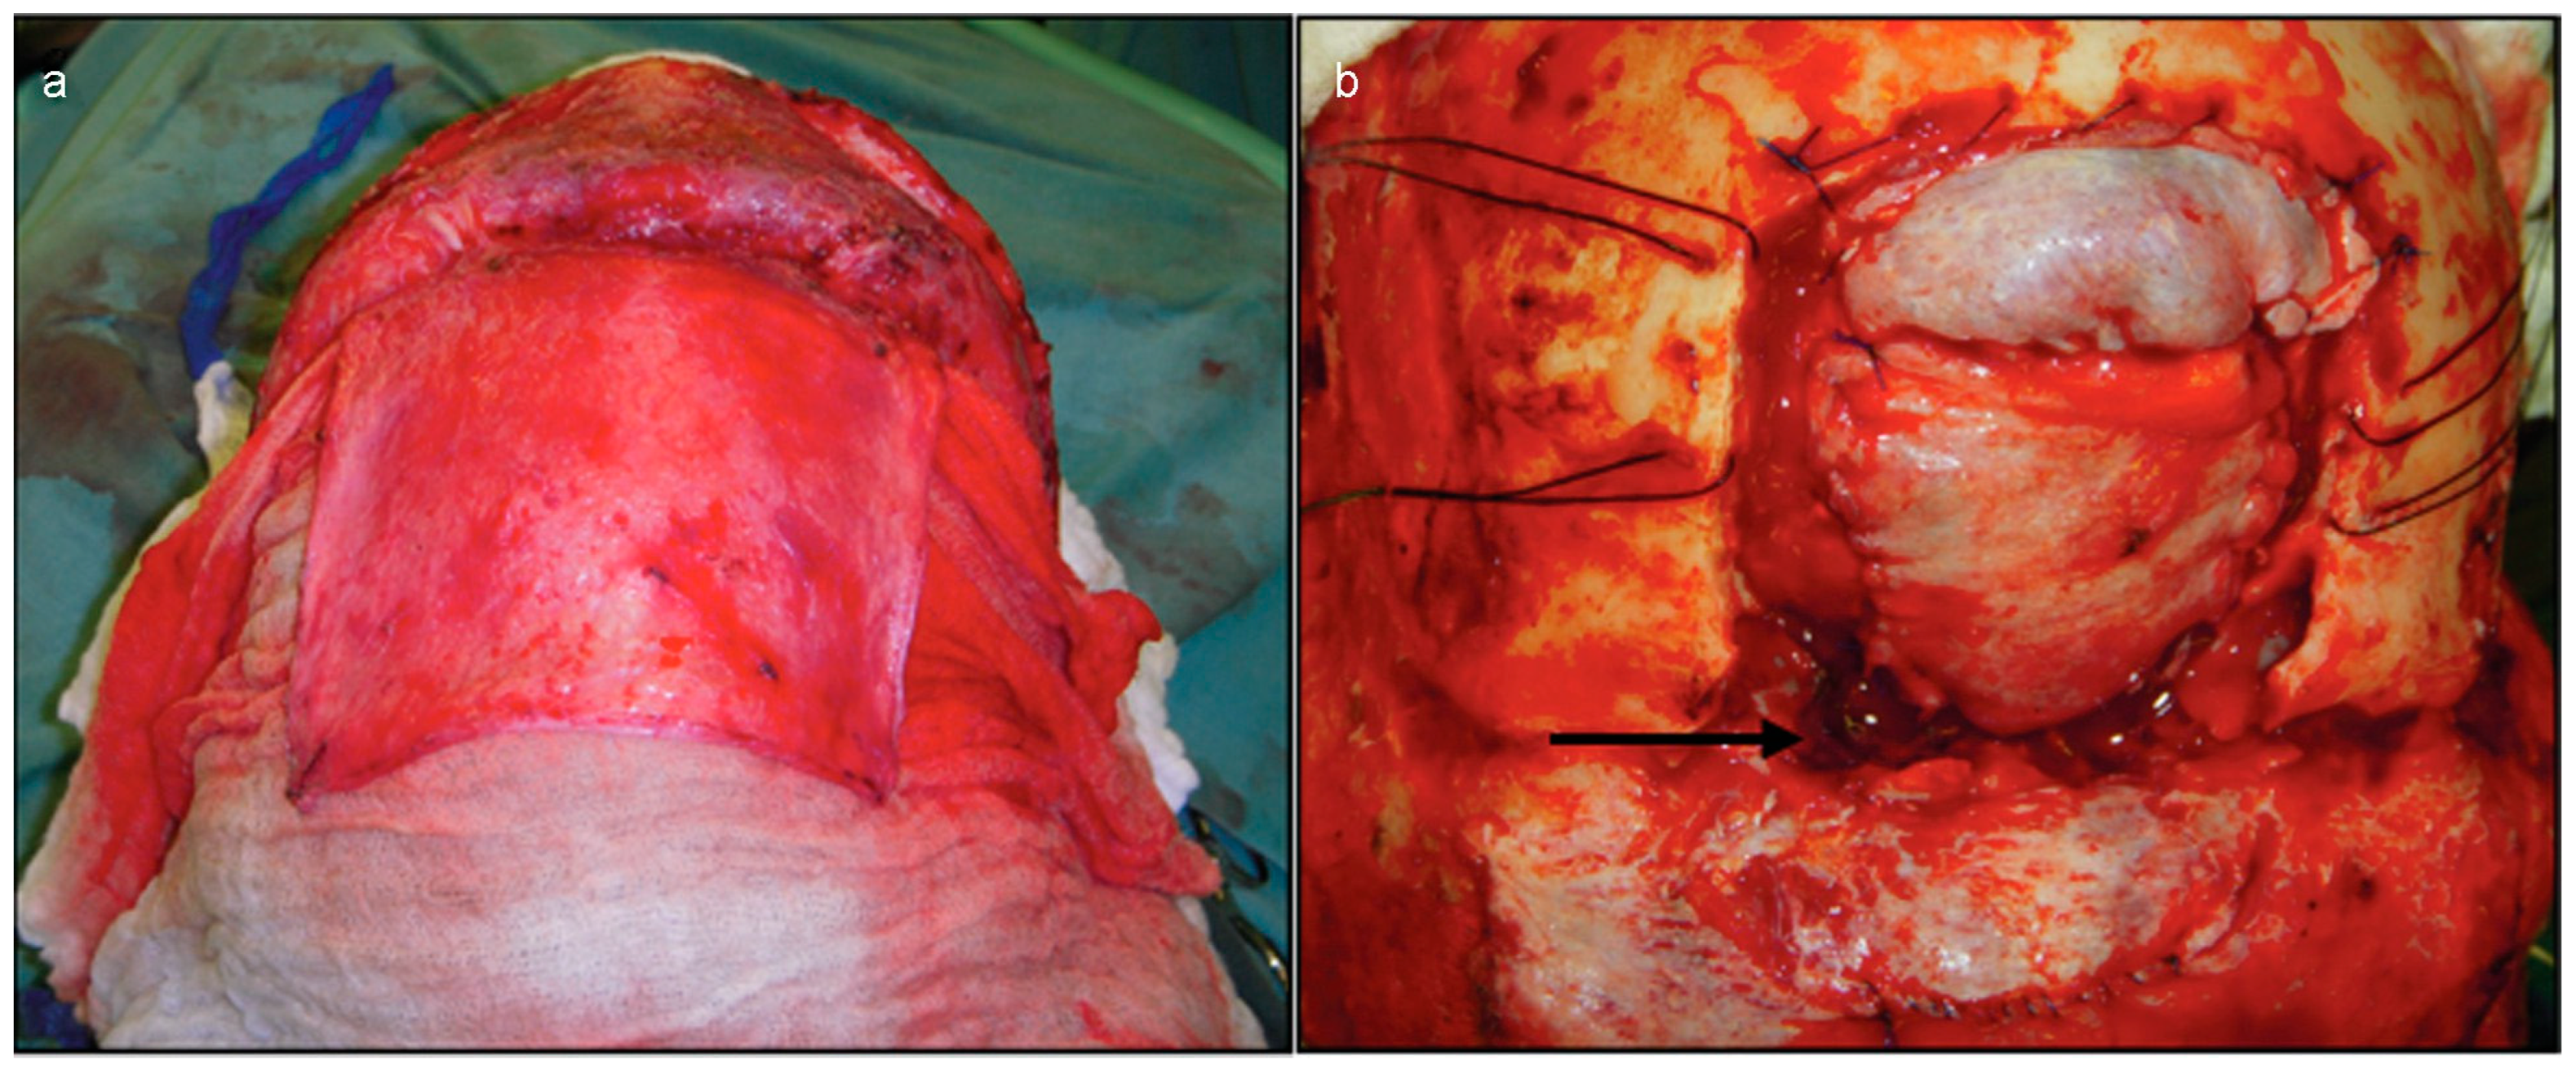

Figure 3. (a) The procedure started with coronal approach, dissection of the loose areolar tissue layer between galea and pericranium. Opening of the pericranial flap that will be the soft-tissue layer above the bony anterior skull base. (b) The frontal craniotomy was performed and the dura mater corrected with galea aponeurotica from parietal region. Note the bone defect below the brain (black arrow).

After that, due to the need for visualization and correction of both dura mater and the fractures, the procedure was performed via bicoronal access, involving the opening of a pericranial flap and a bifrontal craniotomy (Figure 3a). The craniotomy allowed a subfrontal approach and the immediate visualization of dura mater injuries.

Subsequently, the anterior portion of the brain was gently retracted to correct dura mater injuries with primary sutures and soft-tissue graft. In this occasion, a repair was performed using only soft tissue like galea aponeurotica from the parietal region (Figure 3b). The supraorbital portion of the craniotomy was replaced and the pericranial flap was used to cover the skull base defect (Figure 4a). Cranialization of the frontal sinus was done, and the remaining mucosa was removed to avoid mucoceles. The superior portion of the craniotomy was fixed with 1.5-mm titanium plates and mesh (Figure 4b–d).